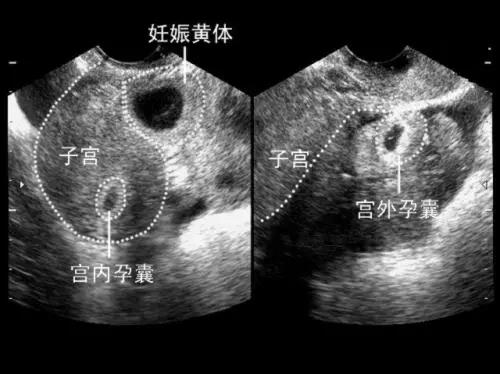

确定是否怀孕,观察妊娠囊、胚胎的大小、数目、位置,判断是单胎还是多胎妊娠。观察胚胎情况,有无胎心搏动,是否有胚胎停止发育。测量头臀长明确孕周,推算预产期。还有重要的一点是排除宫外孕和葡萄胎,看看子宫卵巢有没有异常。